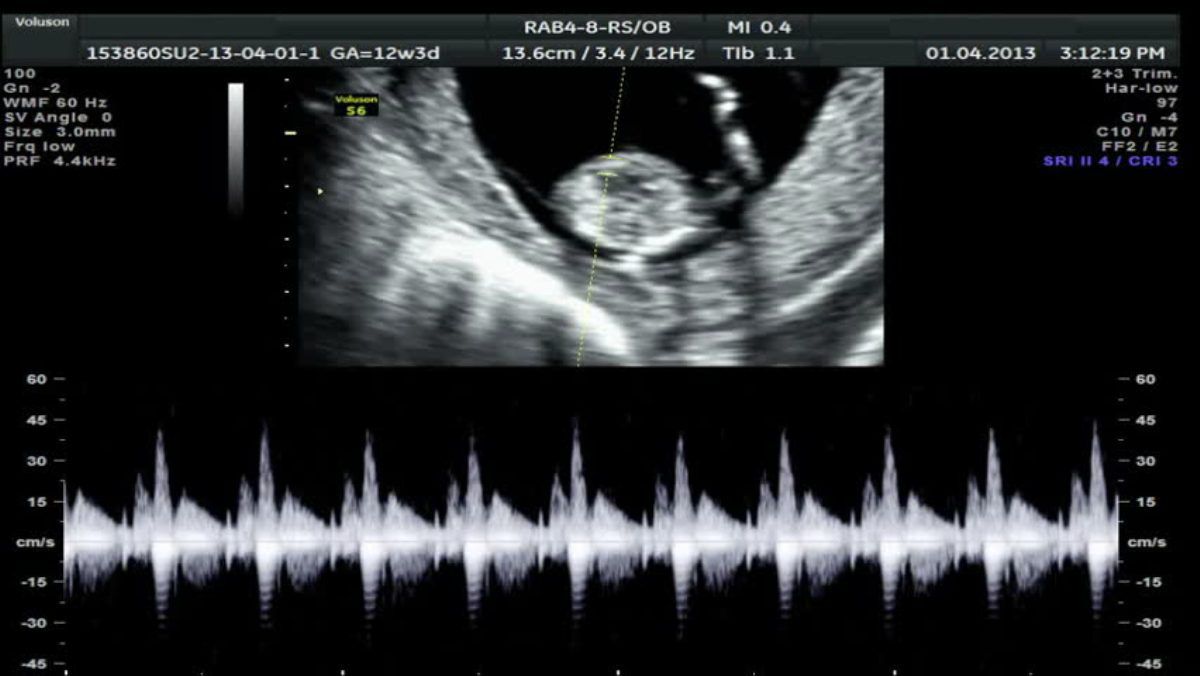

Baby Heart Beat In Utero . An ultrasound can help detect the fetal heartbeat. an arrhythmia is an irregular heart rate — too fast, too slow, or otherwise outside the norm. when does a fetus have a heartbeat? at about five weeks gestation, your baby's heart begins to beat. normal variations in fetal heart rate occur when the baby is moving or asleep. Your doctor or midwife will listen to your. a normal fetal heart rate (fhr) usually ranges from 120 to 160 beats per minute (bpm) in the in utero period. At this point, a normal fetal heart rate is about the. a fetal heartbeat, or your baby’s heartbeat in utero, reflects a functioning cardiovascular system that. While it is not always a cause for. Before about week 8 of.